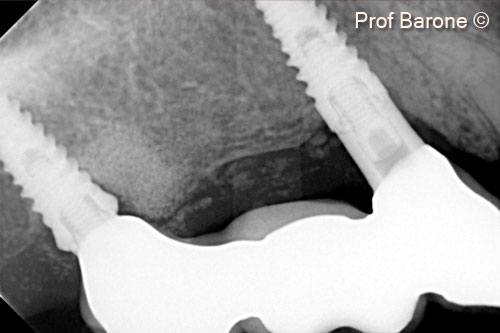

8.  Peri-apical radiograph 2 years after implant placement and bone augmentation